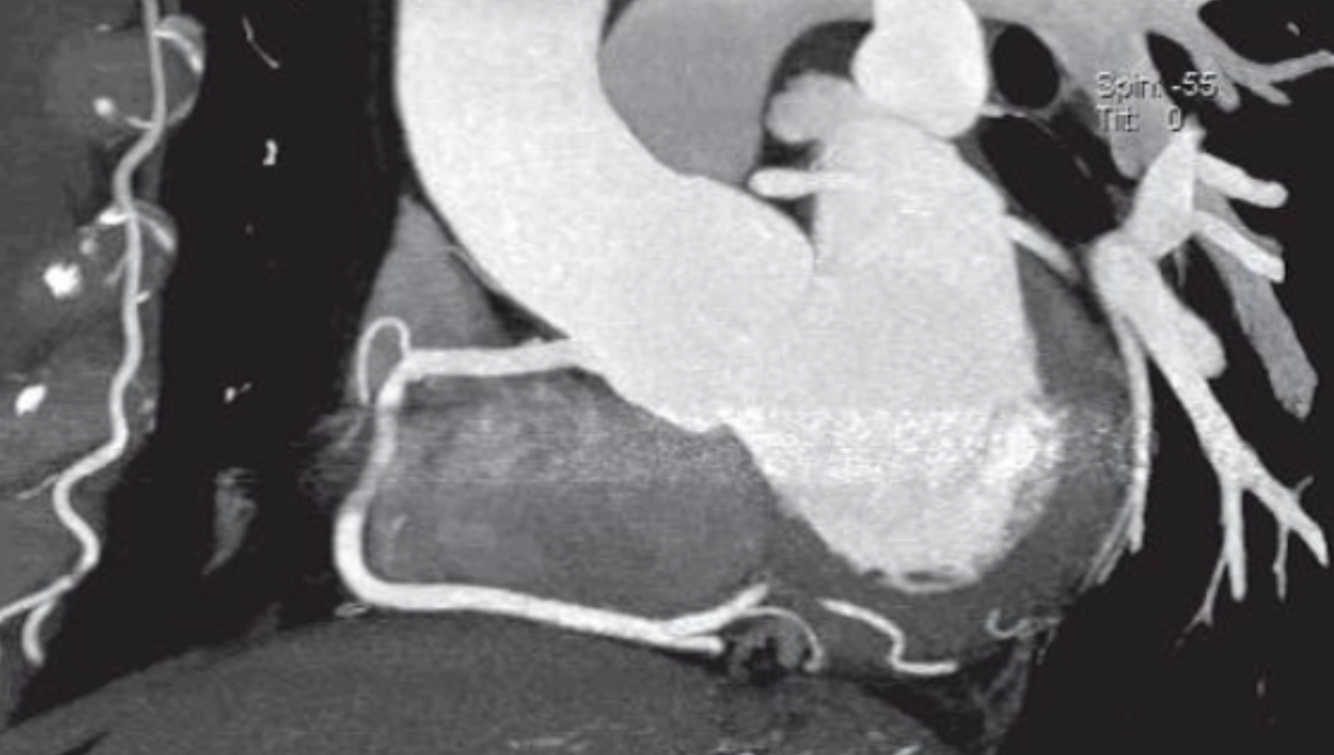

What type of post-processing methods were used to generate the reformatted image shown below?

Multiplanar reformatting and thin slab MIP (5 mm)